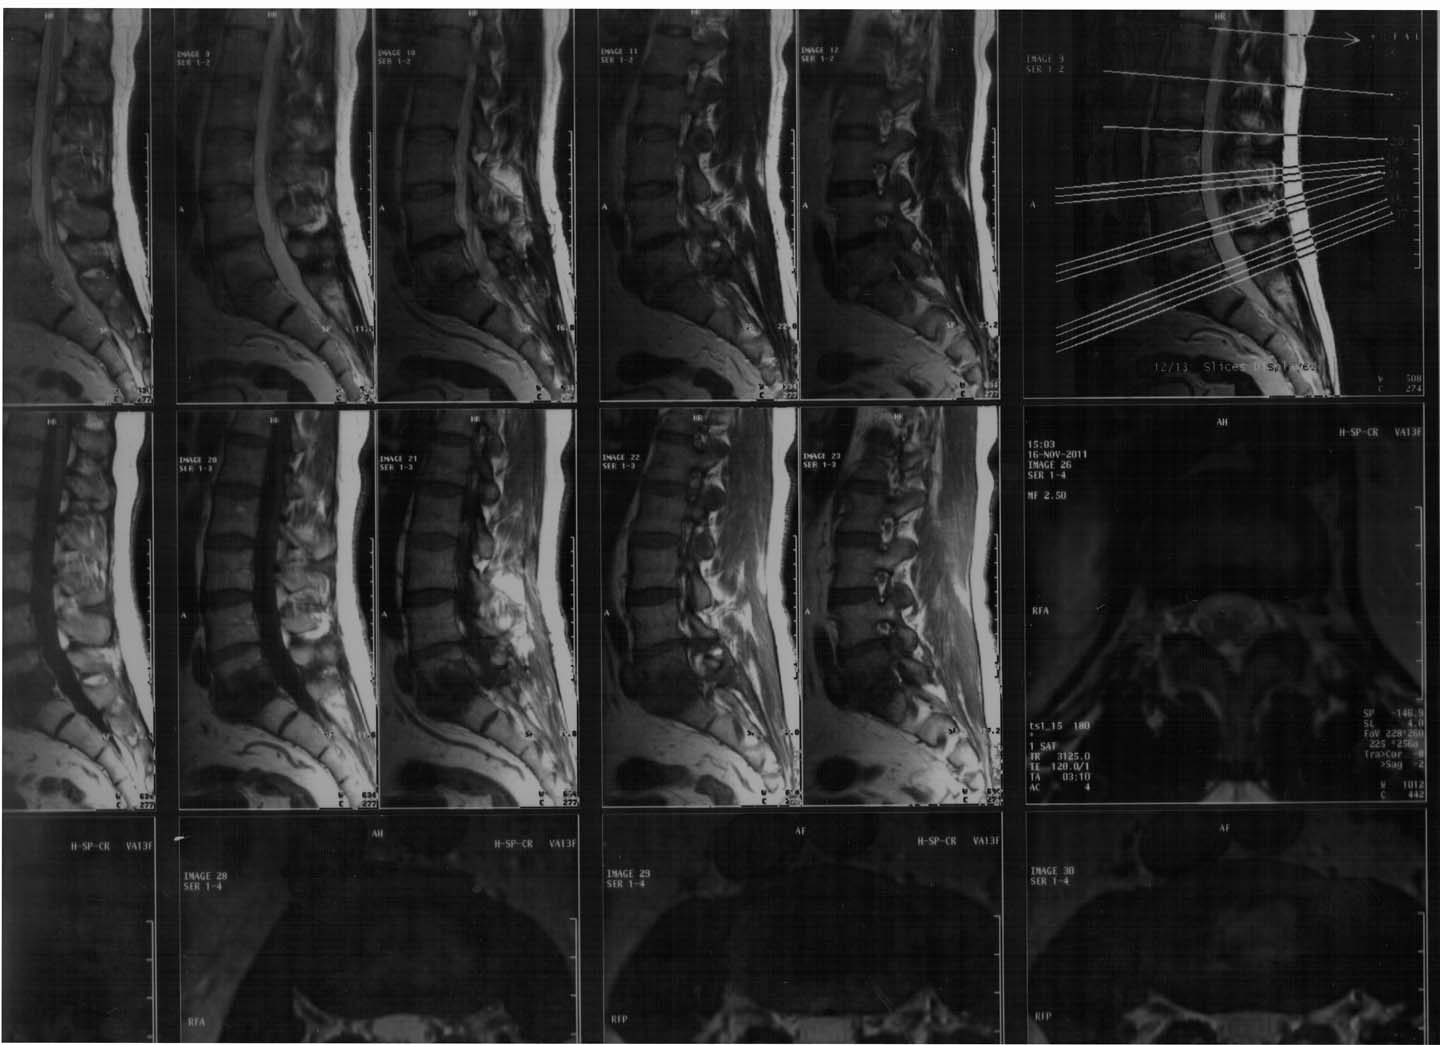

Лечили карипазимом (2 курса по 30 дней). У него была киста почки, так она переросла в рак! В августе 2010 удалили правую почку(pT1вNoMoGII).а в декабре отрезали кусок лёгкого, думали метастаза, но слава Богу оказалась гамартома. Спину практически не лечили, было как-то не до неё, терпел, хотя болит постоянно. Сейчас сделал МРТ с контрастированием Омнискан 10,0 и-новая беда: МР-картина спондилодисцита на уровне L5-S1 сигмента, с наличием превертебрального отграниченного экссудативного компонента. МР- картина стеохондроза; сублигаментарной грыжи (экструзии) дискаL5/S1,дорзальной протрузии диска L4/5. МР- картина деформирующего спондилоза на уровне L5-S1сигмента, спондилоартроза на уровне L4-S1 сигментов. Что нам делать? Это не рак? Мы плачем день и ночь.Он итак, бедный, прошёл через все круги ада, неужели опять? Помогите нам пожалуйста!